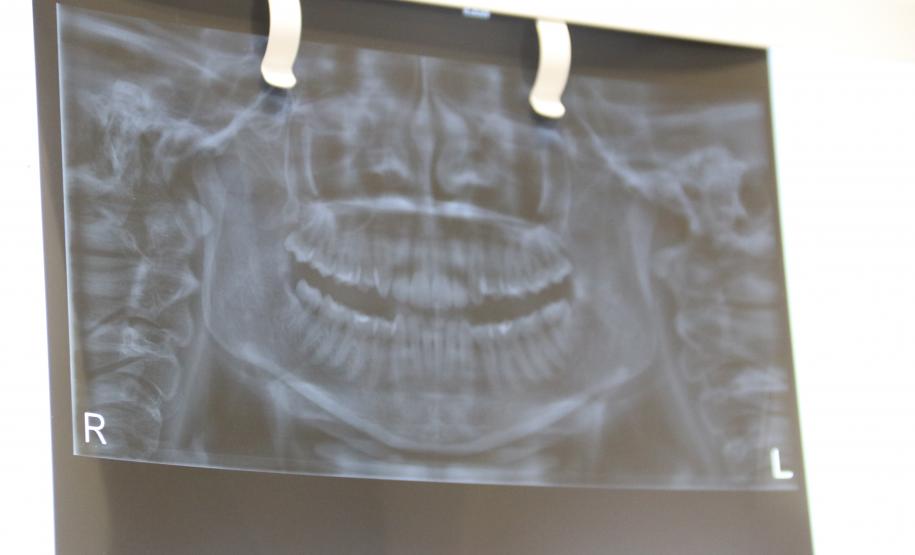

O prontuário odontológico é o conjunto de toda documentação obtida durante o tratamento e mostra uma perspectiva fundamental para os trabalhos dos cirurgiões-dentistas. No IML do Paraná, assim como em várias regiões do País, diversos são os casos de identificação humana possibilitadas por meio de análises das características e especificidades dentais registradas em prontuários.

Os conhecimentos da Odontologia Forense geralmente são adotados para a identificação humana em casos de cadáveres carbonizados, em avançado estado de decomposição, fragmentados e esqueletizados.

“Nesses casos, os profissionais da Polícia Científica chamam os familiares e questionam se a pessoa passou por algum tratamento odontológico. Caso eles tenham conhecimento disso, o dentista da vítima é acionado para que ele possa disponibilizar o prontuário odontológico e, assim, os exames de identificação humana pela arcada dentária possam ser feitos pelos peritos”, explica o diretor da Polícia Científica do Paraná, Luiz Rodrigo Grochocki.

ODONTOLOGIA FORENSE – De acordo com a Polícia Científica, depois da tradicional identificação humana por papiloscopia (impressões digitais), o uso da odontologia forense é a opção mais viável. Além de trazer o resultado rápido, o que agiliza a identificação e liberação do corpo para que a família possa fazer o sepultamento, há menor custo ao Estado do que a identificação por exames de DNA.

REFERÊNCIA NACIONAL - Desde 2013, o Paraná conta com uma comissão permanente de atendimento a desastres dentro da perícia criminal. No início de 2019, a Polícia Científica ganhou destaque nacional por estar na linha de frente da identificação dos corpos resgatados depois do rompimento da Barragem de Brumadinho (MG). Nesse caso, foram feitos exames minuciosos da arcada dentária de vítimas fatais, os quais foram responsáveis pela identificação de muitas delas.